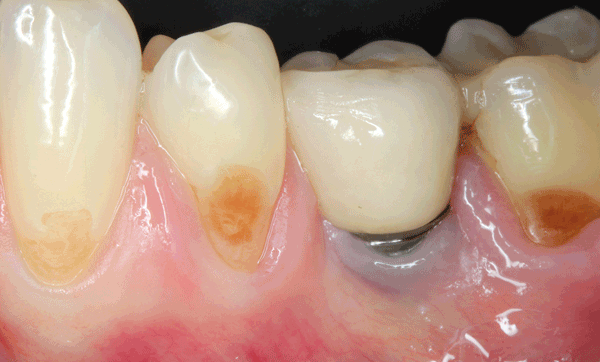

La nécessité de tissu kératinisé autour des dents a fait l’objet d’un long débat en parodontie, et alimente désormais une vive controverse en implantologie. L’importance de sa présence autour des implants reste discutée, et les indications des techniques d’augmentation également. Cette revue narrative a pour but de faire le point sur la littérature dévolue au tissu kératinisé, autour des dents et autour des implants, grâce à dix questions que tout praticien est amené à se poser fréquemment en clinique.

Orban a, pour la première fois, décrit deux parties de la gencive en 1948 : la gencive attachée, fermement adhérente à l’os sous-jacent, et la gencive libre qui la prolonge en direction coronaire, non attachée et délimitant le sillon gingivo-dentaire ou sulcus [1]. Ces deux gencives sont kératinisées et séparées de la muqueuse alvéolaire non kératinisée par la ligne muco-gingivale. La kératinisation est une qualité de l’épithélium qui rend le tissu plus résistant.